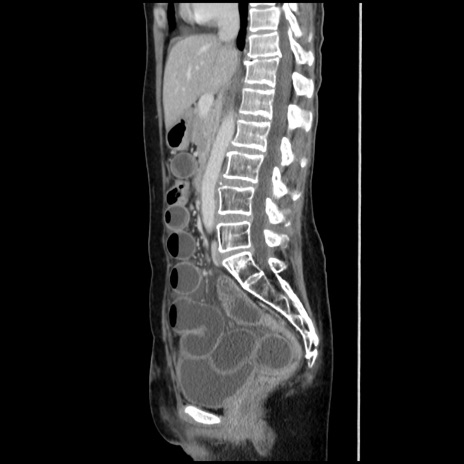

症例32(矢状断像)

【症例】40歳代 女性

【主訴】上腹部痛、嘔気・嘔吐

【現病歴】約9時間前頃から急に上腹部痛、嘔気、嘔吐が出現。改善しないため救急要請。

【既往歴】子宮頚癌(広汎子宮全摘術、放射線療法)、腸閉塞

【身体所見】腹部:平坦、軟、腸雑音亢進、上腹部を中心に腹部全体に圧痛あり。

【データ】WBC 8400、CRP 0.03